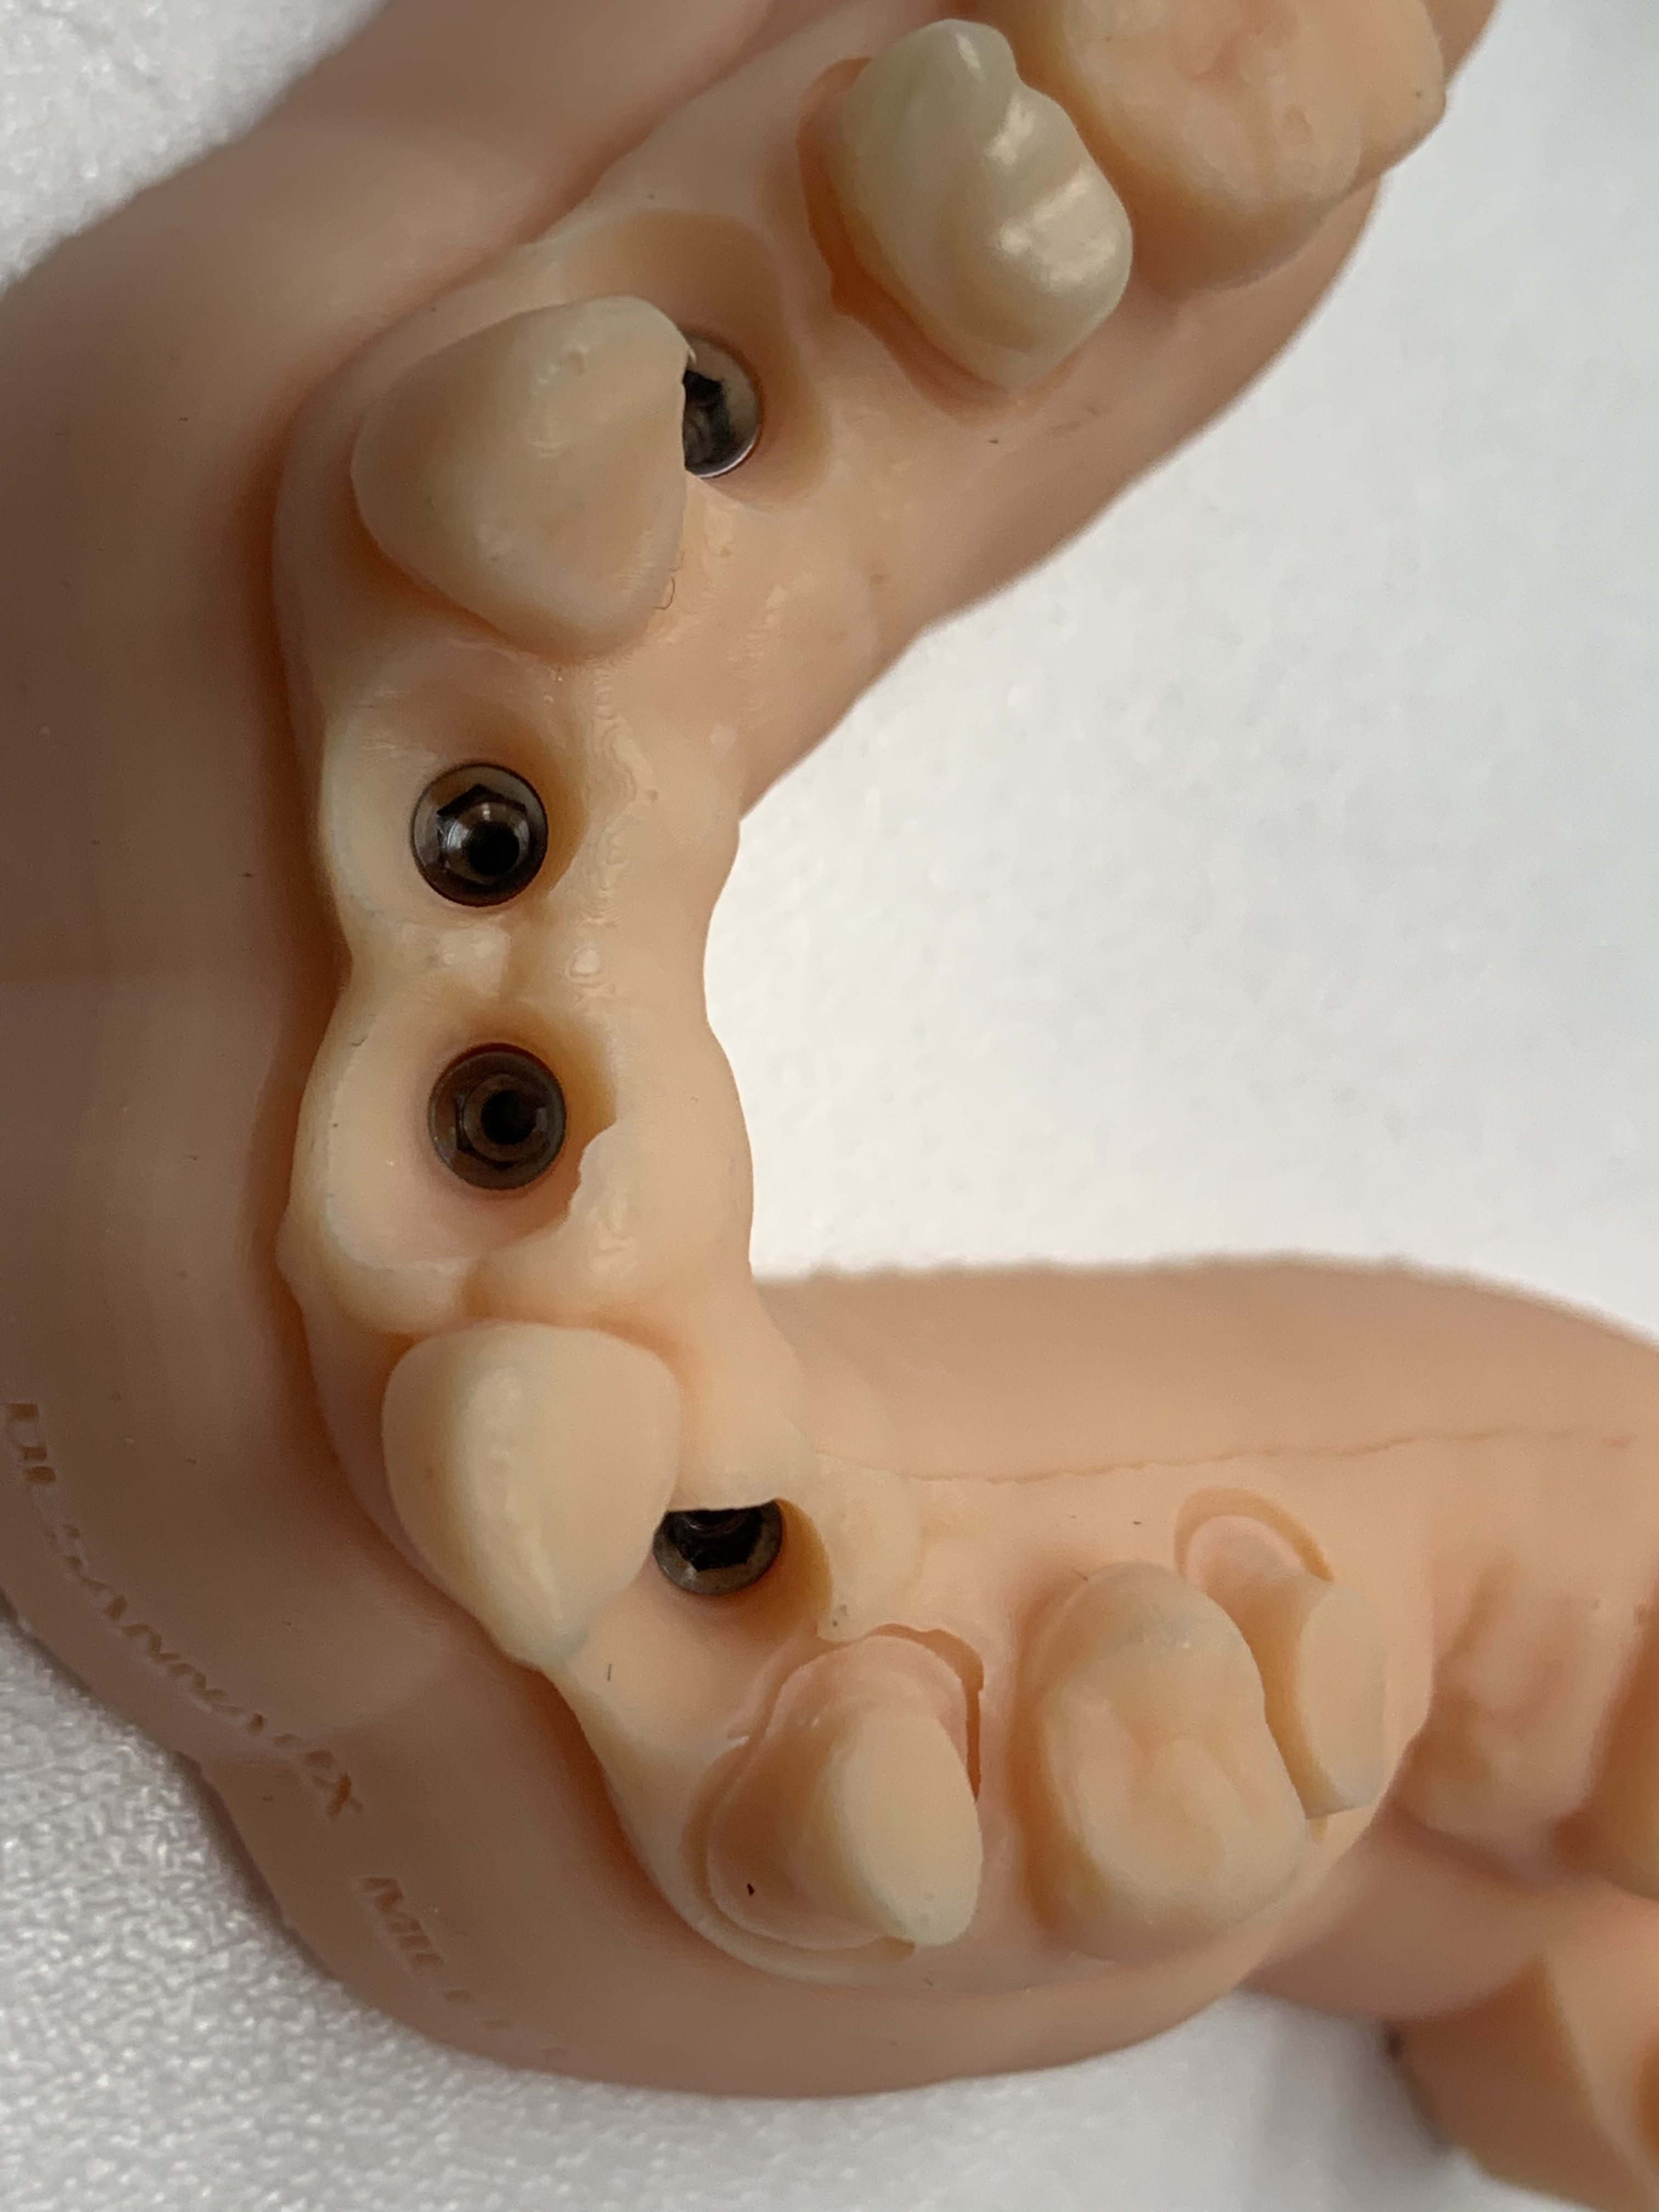

Je suis partie sur une technologie différente qui me permet une maitrise des couts et une qualité idéal pour notre secteur d’activité ( 50 microns)

Quand j’imprime un cube de 20 mm de coté voilà ce que j’obtiens ! C’est pour moi la seul chose qui importe!

Que les stellites adaptent parfaitement dessus et que les analogs frictionnent juste ce qu’il faut

Sans avoir de stries d’impression

Le tout sans facturation de modèles! Car le cout du modèle doit etre inclu dans le prix de la prothese comme c’était le cas avant le numérique